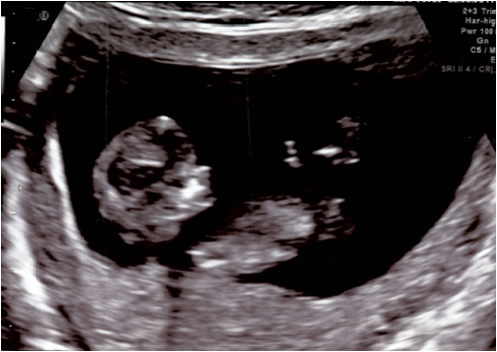

We had an amazing and busy week last week. Like Eddie said, we went for a sonogram on 12/14 that was so amazing. I really cannot believe how much the bean has grown in 2 weeks. There were two really great shots of the little thing as it flipped and moved around. The lady told us again that this is a very energetic little bean! In the first shot you can really tell how much he's grown since the last scan:

In the second shot, the little bean is sucking his thumb!! So so cute: